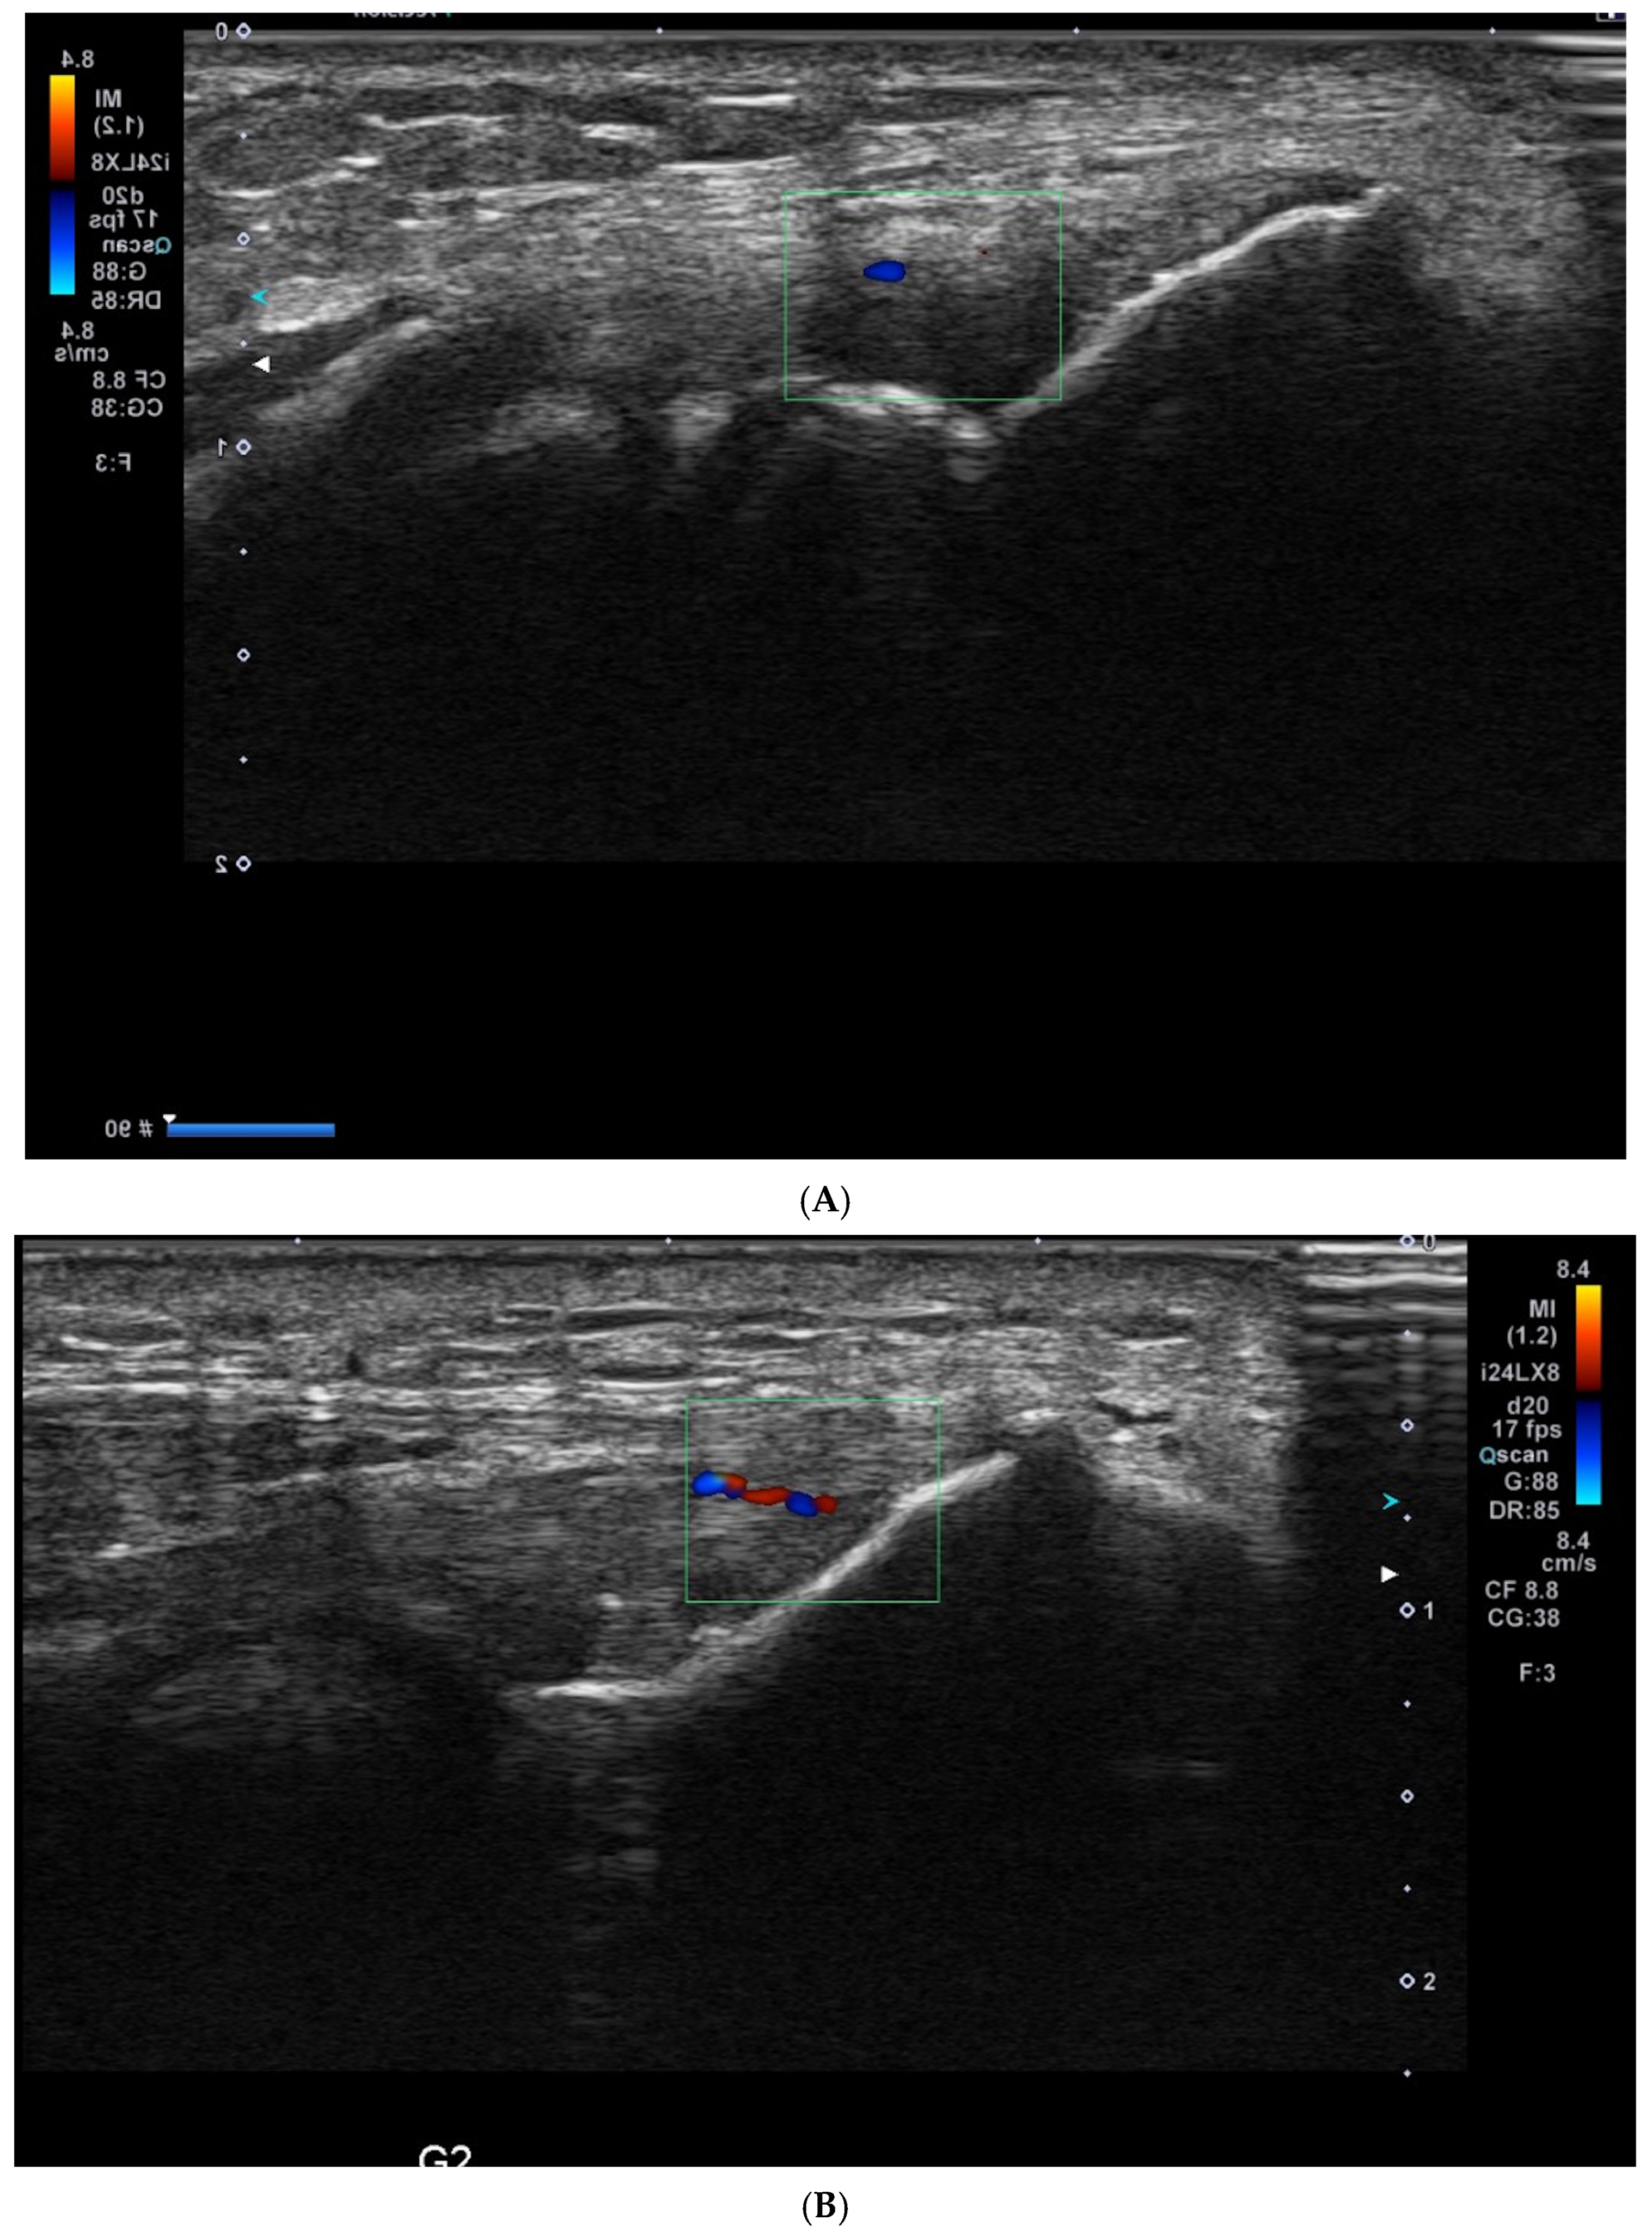

Ultrasound (USG) evaluations were conducted jointly by two specialists following the clinical diagnosis. The physicians performing the USG were blinded to the patients’ clinical outcomes and treatment details. The USG procedure was repeated three months post-treatment. Color Doppler imaging (frame rate 10–15 Hz) and superb microvascular imaging (SMI; frame rate > 50 Hz) were performed using the Toshiba Aplio 500 USG system with a high-frequency linear array transducer. Vascular activity on color Doppler imaging was graded on a scale of 0 to 4: Grade 0 = no activity, Grade 1 = single vessel, Grade 2 = Doppler activity < 25%, Grade 3 = Doppler activity 25–50%, and Grade 4 = Doppler activity > 50% [19] (Figure 2).

Figure 2.

Ultrasound images illustrating vascularity grading in lateral epicondylitis using Doppler imaging: (A) Grade 1: single-vessel activity; (B) Grade 2: Doppler activity ≤ 25%; (C) Grade 3: Doppler activity between 25 and 50%; and (D) Grade 4: Doppler activity ≥ 50%.